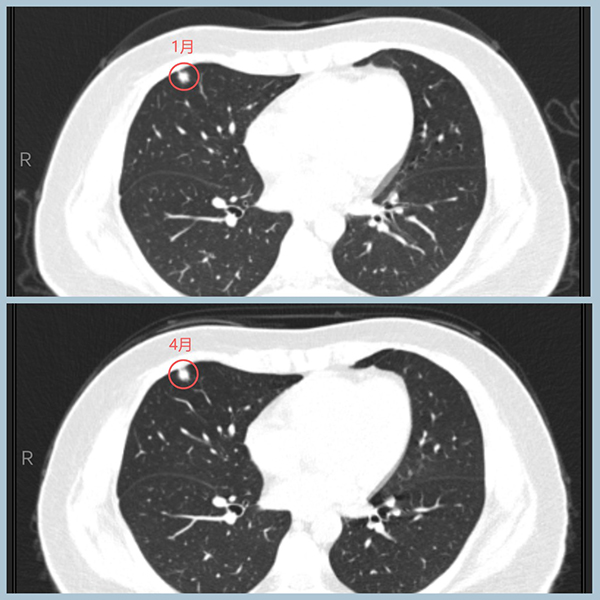

1、右肺两处结节,较大的在右中叶,恶性征象比较明显,3个月内有肉眼可见的变化:更加饱满,距胸膜更近。较小的在右下叶背段,约3mm,为纯磨玻璃结节,无明显变化,不典型增生可能大,可一并手术切除。